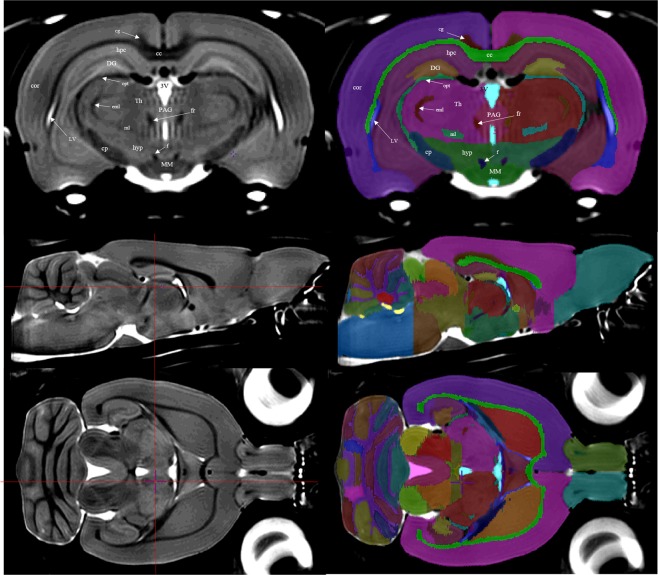

Figure 2.

Left column: the averaged brain, which served as a template for structural delineation. Red crosshairs on transverse and sagittal view (middle and bottom) indicate the positions of the other planes. Right column: the atlas file is overlaid onto the template file. Delineation and refinement were primarily performed using the coronal sections, though further refinement was done in both the sagittal and axial planes. Top row: annotated over the left hemisphere of both coronal images are the structural regions that the label tags represent. Middle and Bottom row show transverse and sagittal views respectively; CC, corpus callosum and external capsule; cg, cingulum; cor, cortex; cp, cerebral peduncles; DG, dentate gyrus; eml, external medullary lamina; f, fornix; fr, fasciculus retroflexus; hyp, hypothalamus; hpc, hippocampal CA subfields; LV, lateral ventricle; ml, medial lemniscus; MM, mammillary bodies; opt, optic tract; PAG, periaqueductal gray; 3 V, third ventricle.

Segmentation was performed by a single investigator (D.G.) based on the combined observations of T2-weighted tissue contrast as well as the P&W paper atlas2. Anatomical regions were delineated using the Display Software of the MINC-toolkit-v2 version 1.9.16 (https://github.com/BIC-MNI/minc-toolkit-v2)29. Positive grayscale contrast was used for all manual segmentation tasks. Regions were delineated on each coronal slice individually, and bilaterally, from the olfactory bulb to the first slice of spinal cord. In total, 71 anatomical structures or substructures were manually identified and included in the atlas. In certain specific regions, when boundaries were not obvious on basis of image contrast, the P&W atlas and anatomical landmarks were used to identify boundaries. Such regions are identified in further detail in the Supplementary section. The majority of the segmentation was done in the coronal view, however both the sagittal and axial views were used to ensure accuracy from other perspectives (Fig. 2).